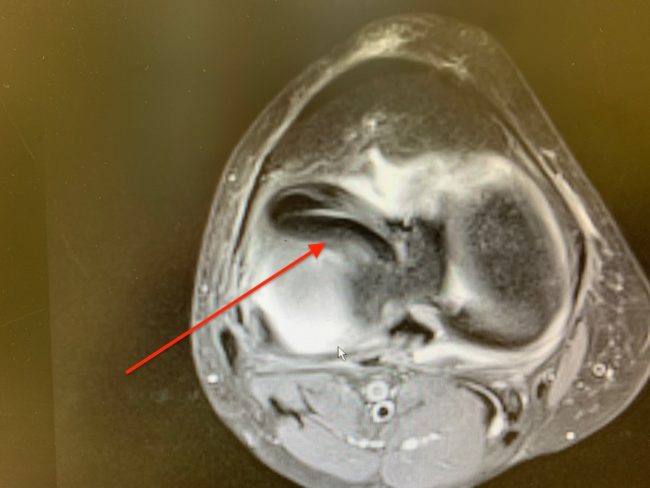

Chonodromalacja – uszkodzenia chrząstki

Powracam z tematem chrząstki stawowej. Informacja o uszkodzeniu chrząstki deprymuje pacjenta, a w szczególności sportowca. Jest on jednak pełen wiary w możliwość medycyny i leczenia. Niestety sprawa jest bardzo złożona… Nieleczone uszkodzenia chrząstki prowadzą do zniszczenia stawu, a w konsekwencji do ograniczenia jego funkcji i ograniczenia ruchomości.